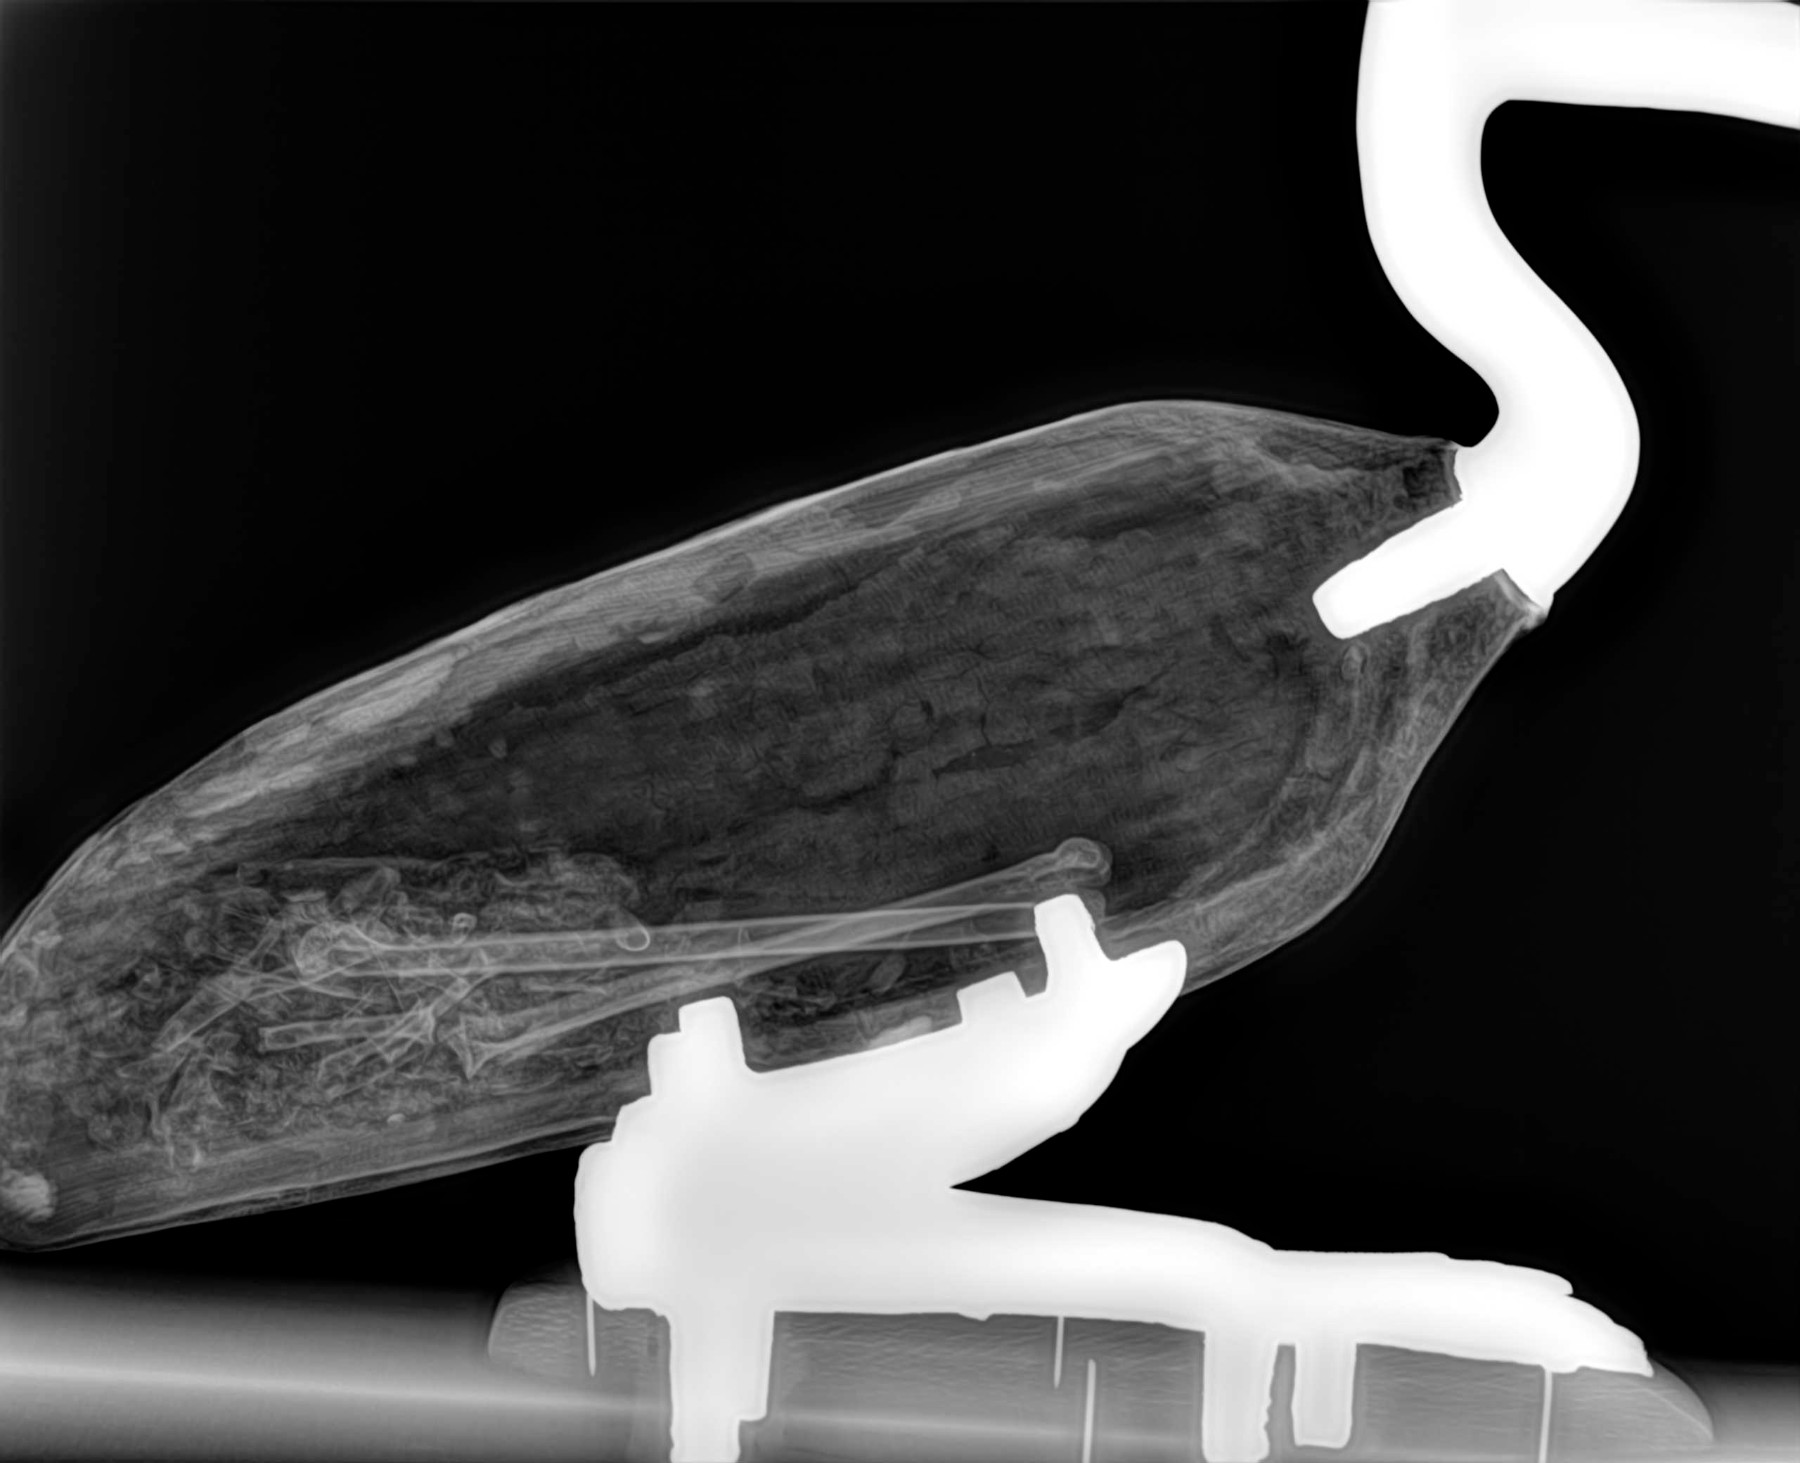

Radiología Digital como Herramienta Complementaria en el Dictamen de Bienes Muebles

Desde el descubrimiento de los rayos “X” y las placas radiográficas por Wilhelm Conrad Roentgen y su posterior difusión a través de la Asociación Físico médica de Wurzburg el 28 de diciembre de 1895, que fue la primera asociación que habló de los nuevos rayos que podían penetrar el cuerpo y fotografiar los huesos, ha habido muchos cambios tanto en la forma de obtener, procesar e incluso en la forma de visualizar, manejar y almacenar las placas radiográficas.